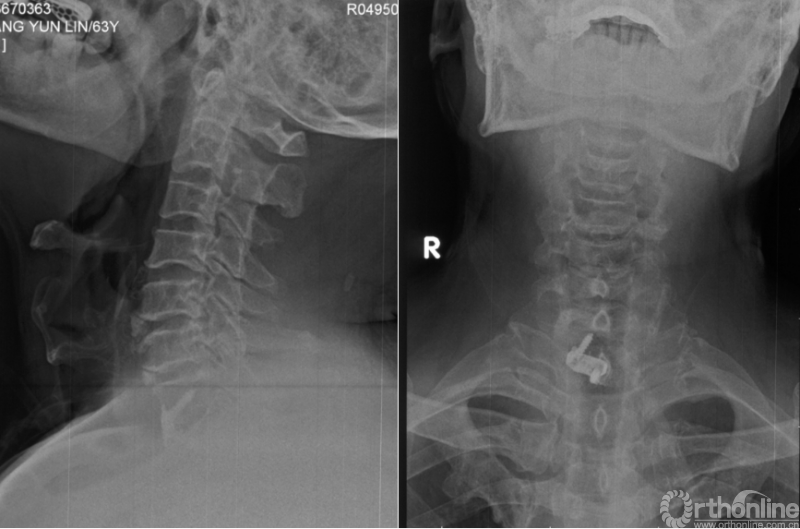

心电图提示窦性心律,ST-T轻度压低。胸部X线、胸部CT、心脏彩超及心肌酶均未见明显异常。颈椎X线提示颈椎退变及前纵韧带骨化(图A),颈椎MRI提示C7-T1椎间盘突出导致右侧C8神经根严重压迫(图B)。经科室讨论明确诊断为神经根型颈椎病及颈源性胸痛后,进行C7/T1的ACDF手术(图C),术后患者胸痛症状明显好转(VAS=2分),右手麻木症状消失,肌力也逐渐恢复。

图C 术后过伸位和正位片